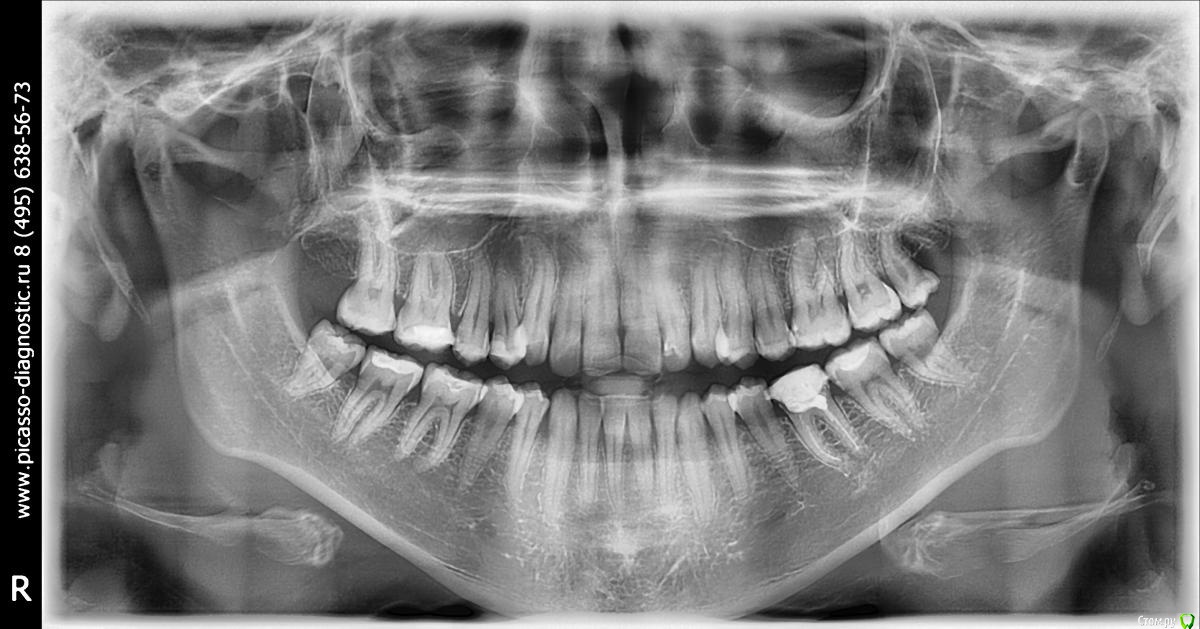

Led_9 Опубликовано 4 марта, 2015 Поделиться Опубликовано 4 марта, 2015 Добрый день!Назрел вопрос насущный по исправлению прикуса. То, что надо ставить брекеты под вопрос не ставлю, ситуация сложная. Была на консультациях у двух специалистов. И уже пора определяться с тем, у кого делать. Но одолевают сомнения, после последних посещений.Итак. Клиника №1.Врач сделав расчет, слепки и т.д. говорит, что удалять ничего не придется для лечения. Пожалуй,в этой клинике я бы осталась, врач вызывает только положительные эмоции. Но цены на работы кусачие.Клиника №2.По первому посещению никаких вопросов к ортодонту не возникает. На второе посещение я привезла слепки, сделанные в первой клинике, снимки и расчет первого врача.Врач говорит, что наверное удалять сверху ничего не будет. А вот про удаление нижних пока сказать не может, ибо в ходе лечения может потребоваться их удаление. Собственно, сам вопрос который назрел таков: Возможно ли удаление в процессе лечения прикуса брекетами? Кто-то сталкивался? Насколько это сложно, поскольку изначально рассматривали удаление 6к снизу (поскольку 1ой по сути нет - стоит реставрация из пломб. материала), ведь на 6ки приклеиваются брекеты? Сейчас доктор второй клиники говорит о возможности удаления 8к снизу в ходе лечения. Хорошо это, что доктор обсуждает такую возможность перед началом лечения (имею ввиду именно удаление в процессе)? Или может быть в первом случае доктор не совсем прав, что не обсуждает таких вариантов развития событий? Правильно ли я понимаю, что доктор закупает систему исходя из того как он решил лечить сначала? И строит план лечения из того наличия зубов, с чем решил работать? Буду признательна, если со мной поделятся своим опытом и пациенты и врачи, поскольку для меня это не простое решение, и я очень боюсь "плохих" последствий, если вдруг столкнусь с некачественной ортодонтией.... Ссылка на комментарий

Led_9 Опубликовано 5 марта, 2015 Автор Поделиться Опубликовано 5 марта, 2015 Доброе утро! Спасибо за ответ. Снимки я не прикрепила специально, т.к. не хотела получить консультацию по плану лечения, а хотела получить совет именно на что следует обратить внимание при выборе доктора (вполне возможно что я зря засомневалась и такой подход абсолютно нормален). Но все же снимки прикрепляю. Ссылка на комментарий